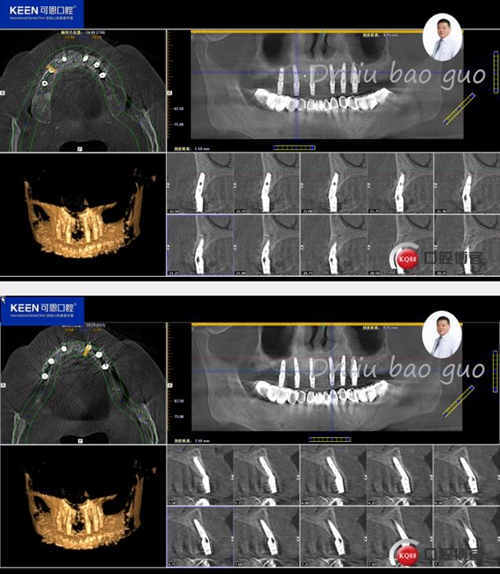

手術前種植軟件設計方案

3.jpg

4.jpg

5.jpg

6.jpg